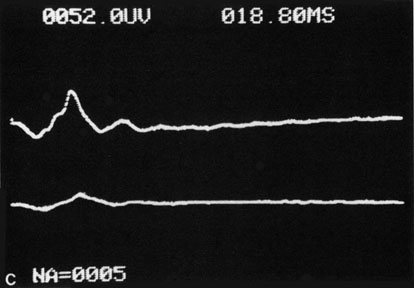

Hypoperfusion retinopathy is characterized by dot and blot hemorrhages in the midperiphery of the fundus, by venous tortuosity and engorgement, by microaneurysms, and by the occasional sludging of blood within the veins. Fluorescein angiography may show areas of capillary nonperfusion; it may also show microaneurysms in the midperiphery and slow arm to retina or arteriovenous transit time (Fig. 9A and 9B).174 The condition does not usually affect the posterior pole, and patients typically have normal visual acuity, although an occasional patient may have macular edema.174 The entire periphery of the eye is usually affected, although there may be more hemorrhages in one quadrant than another. Patients occasionally experience ocular discomfort or eye pain despite normal intraocular pressure. Reduction of the ophthalmic arterial pressure is a pathognomonic feature. Disc edema and disc collaterals are generally not present. The electroretinogram shows abnormalities in both the a- and b-waves (see Fig. 9C).

Fig. 9. Intravenous fluorescein angiogram of a patient with hypotensive or hypoperfusion retinopathy. A: There is a marked delay in the choroidal and retinal filling. B: In the recirculation of the angiogram, there is a characteristic staining of both arteries and veins. C: Electroretinogram shows normal a- and b-waves in the normal right eye (upper tracing) and marked redirection of the a- and b-waves in the affected left eye (lower tracing).